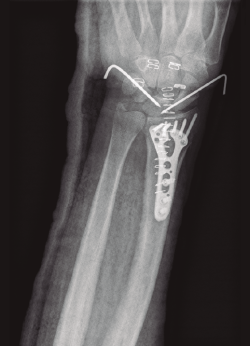

- Reducción abierta de la fractura y posicionamiento inicial del material de fijación interna, que en todos los casos se trató de una placa bloqueada de bajo perfil y tornillos distales poliaxiales (Geminus® Skeletal Dynamics, Miami, Florida), bajo control radioscópico.

- Artroscopia de muñeca con sistema de tracción longitudinal a 10 N y vías artroscópicas estándar 3-4 y 6R para evaluar la articulación radiocarpiana y las vías mediocarpiana ulnar (MCU) y radial (MCR) en el caso de la articulación mediocarpiana, utilizando para ello una óptica de 2,3 mm y 30°(2,17), mediante técnica de artroscopia en seco(23)(Figura 2). En este tiempo quirúrgico artroscópico se evaluó: la presencia de escalón articular, la rotación de los fragmentos articulares y la existencia de lesiones asociadas al nivel del complejo del fibrocartílago articular (CFCT), así como al nivel de los ligamentos extrínsecos e intrínsecos de la muñeca(17)(Figura 3). En primer lugar, se evalúo la articulación radiocarpiana y, a continuación, la articulación mediocarpiana.

- Fijación definitiva de la placa controlando, mediante visualización artroscópica directa, el correcto posicionamiento de los tornillos distales.